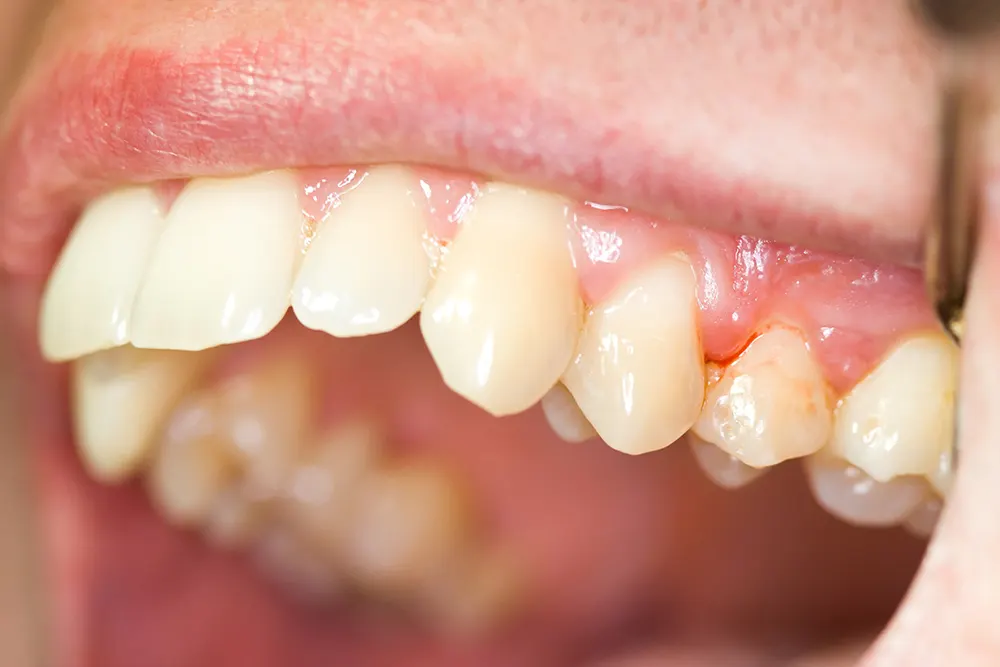

• Nướu trở nên sưng và có thể mềm khi chạm. Nướu bình thường có màu hồng nhạt. Trong trường hợp viêm nướu, chúng có thể trở nên đỏ, thậm chí có thể chuyển sang màu đỏ đậm.

• Mảng bám răng và cao răng bám trên bề mặt răng, nhất là vùng cổ răng.

• Trong các trường hợp nặng, nướu có thể bị tụt xuống , làm lộ thêm phần của chân răng và tạo điều kiện cho vi khuẩn phát triển gây mất nướu và xương.